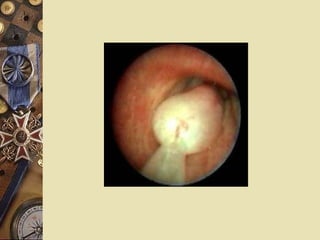

Evaluation 2.Bronchoscopy   Evaluating the proximal airways for lesions. Assessing the cause of hemoptysis Localizing the source of hemoptysis